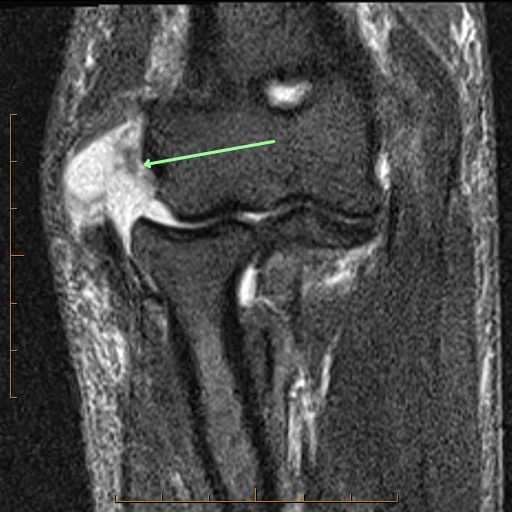

This 65-year-old presents for an elbow MRI with no known injury. Can you name the components of lateral stabilizers and what is missing? Let the arrows be your clue.

Dynamic stabilizers are musculotendinous extensors and these are ruptured from their origin. Static stabilizers include:

- Lateral ulnar collateral ligament- intact (LUCL - double arrows, image one)